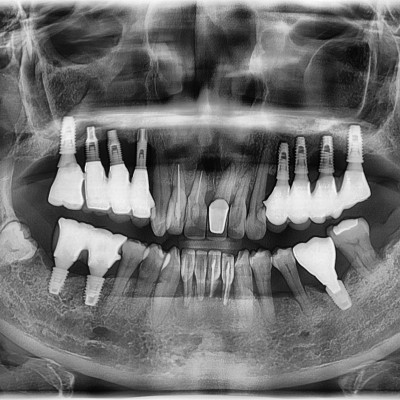

임플란트 재수술 #12.13.22 타원 임플란트 제거 후 임플란트 수술+치조골 이식술 시행하였습니다.

작성자 이턱이 작성일 01-27 조회 109